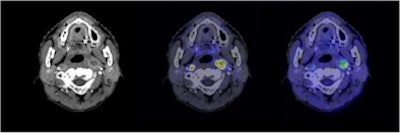

![]() |

| Semiconductor PET images (coregistered with CT images) of nasopharyngeal cancer, using FDG (center image) and F-18 fluoromisonidazole (FMISO) (right image) tracers. The new PET system clearly reveals the different distribution between metabolism and hypoxia in the left neck lymph node metastasis. |

The average absolute volume of GTVNEW was 15.7 mL, compared to 34.0 mL for GTVCONV. Regardless of the order in which the scans were conducted, the GTVNEW volumes were smaller than the GTVCONV volumes for all 12 patients. There were no statistically significant differences between the maximum and mean doses to the PTV for the two regimes.